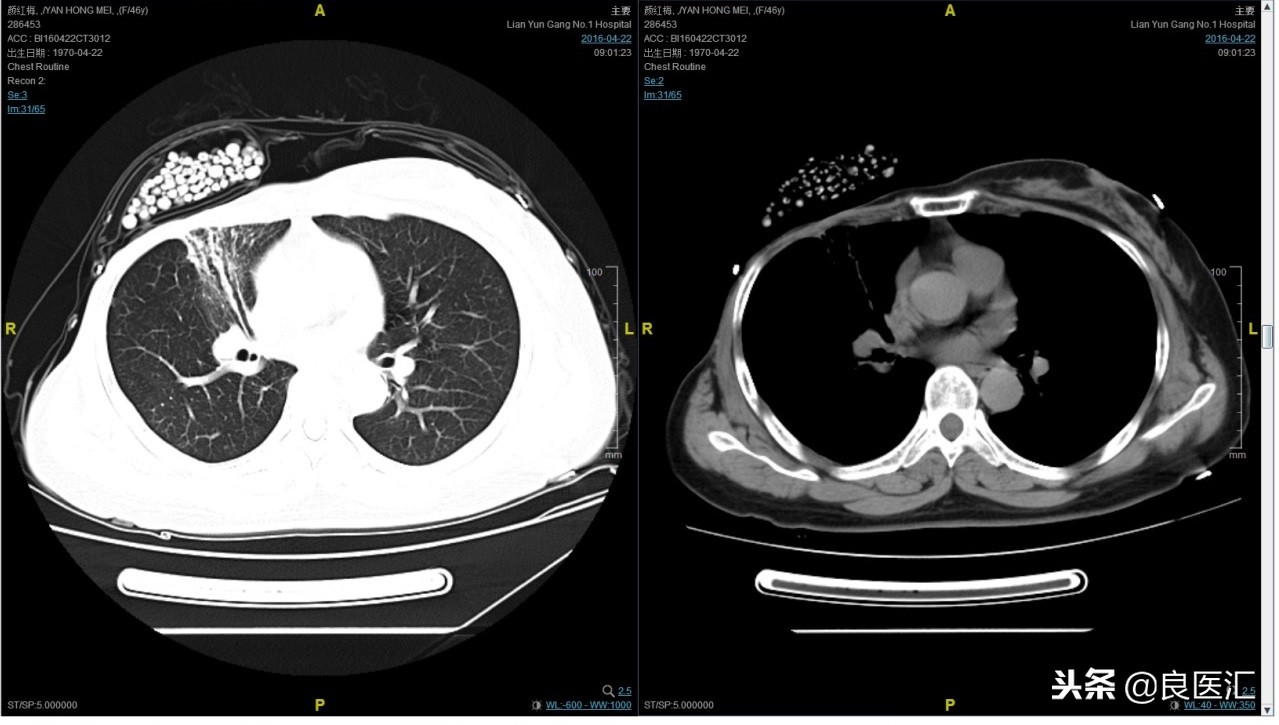

期间2016-4-22复查CT如下:

2016-7-5化疗结束后复查CT,疗效评价稳定。